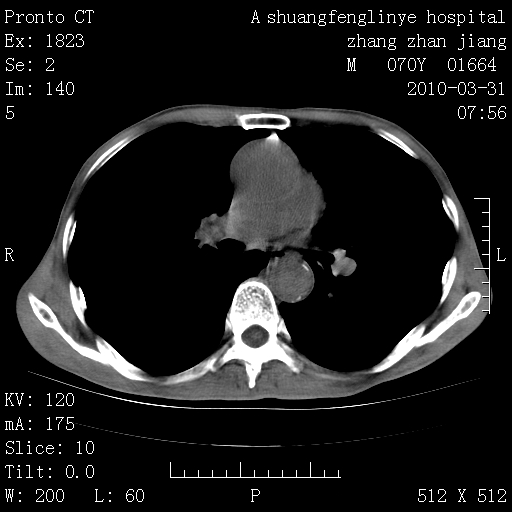

标题: CT25450:肺结核?

双上肺继发型tb并左上空洞形成,主动脉冠脉钙化。

支持:继发性肺结核伴空洞形成!建议纤支镜检查待出外周围型肺癌可能!

1)两肺上叶继发性肺结核并左肺上叶空洞形成。2)冠状动脉及主动脉钙化。